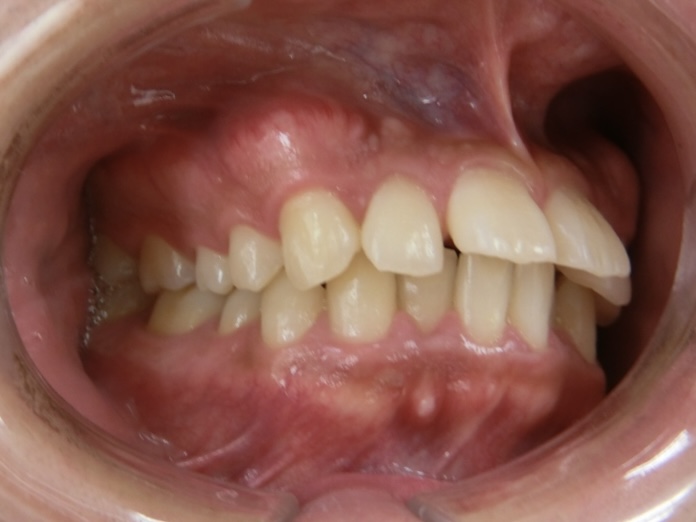

上顎の前歯が大きく突出しています

明らかに前歯の突出感が改善し、患者様はこの時点でとても喜ばれていました

矯正治療終了時 部分矯正ということもあり、短期間で矯正治療を終了することができました